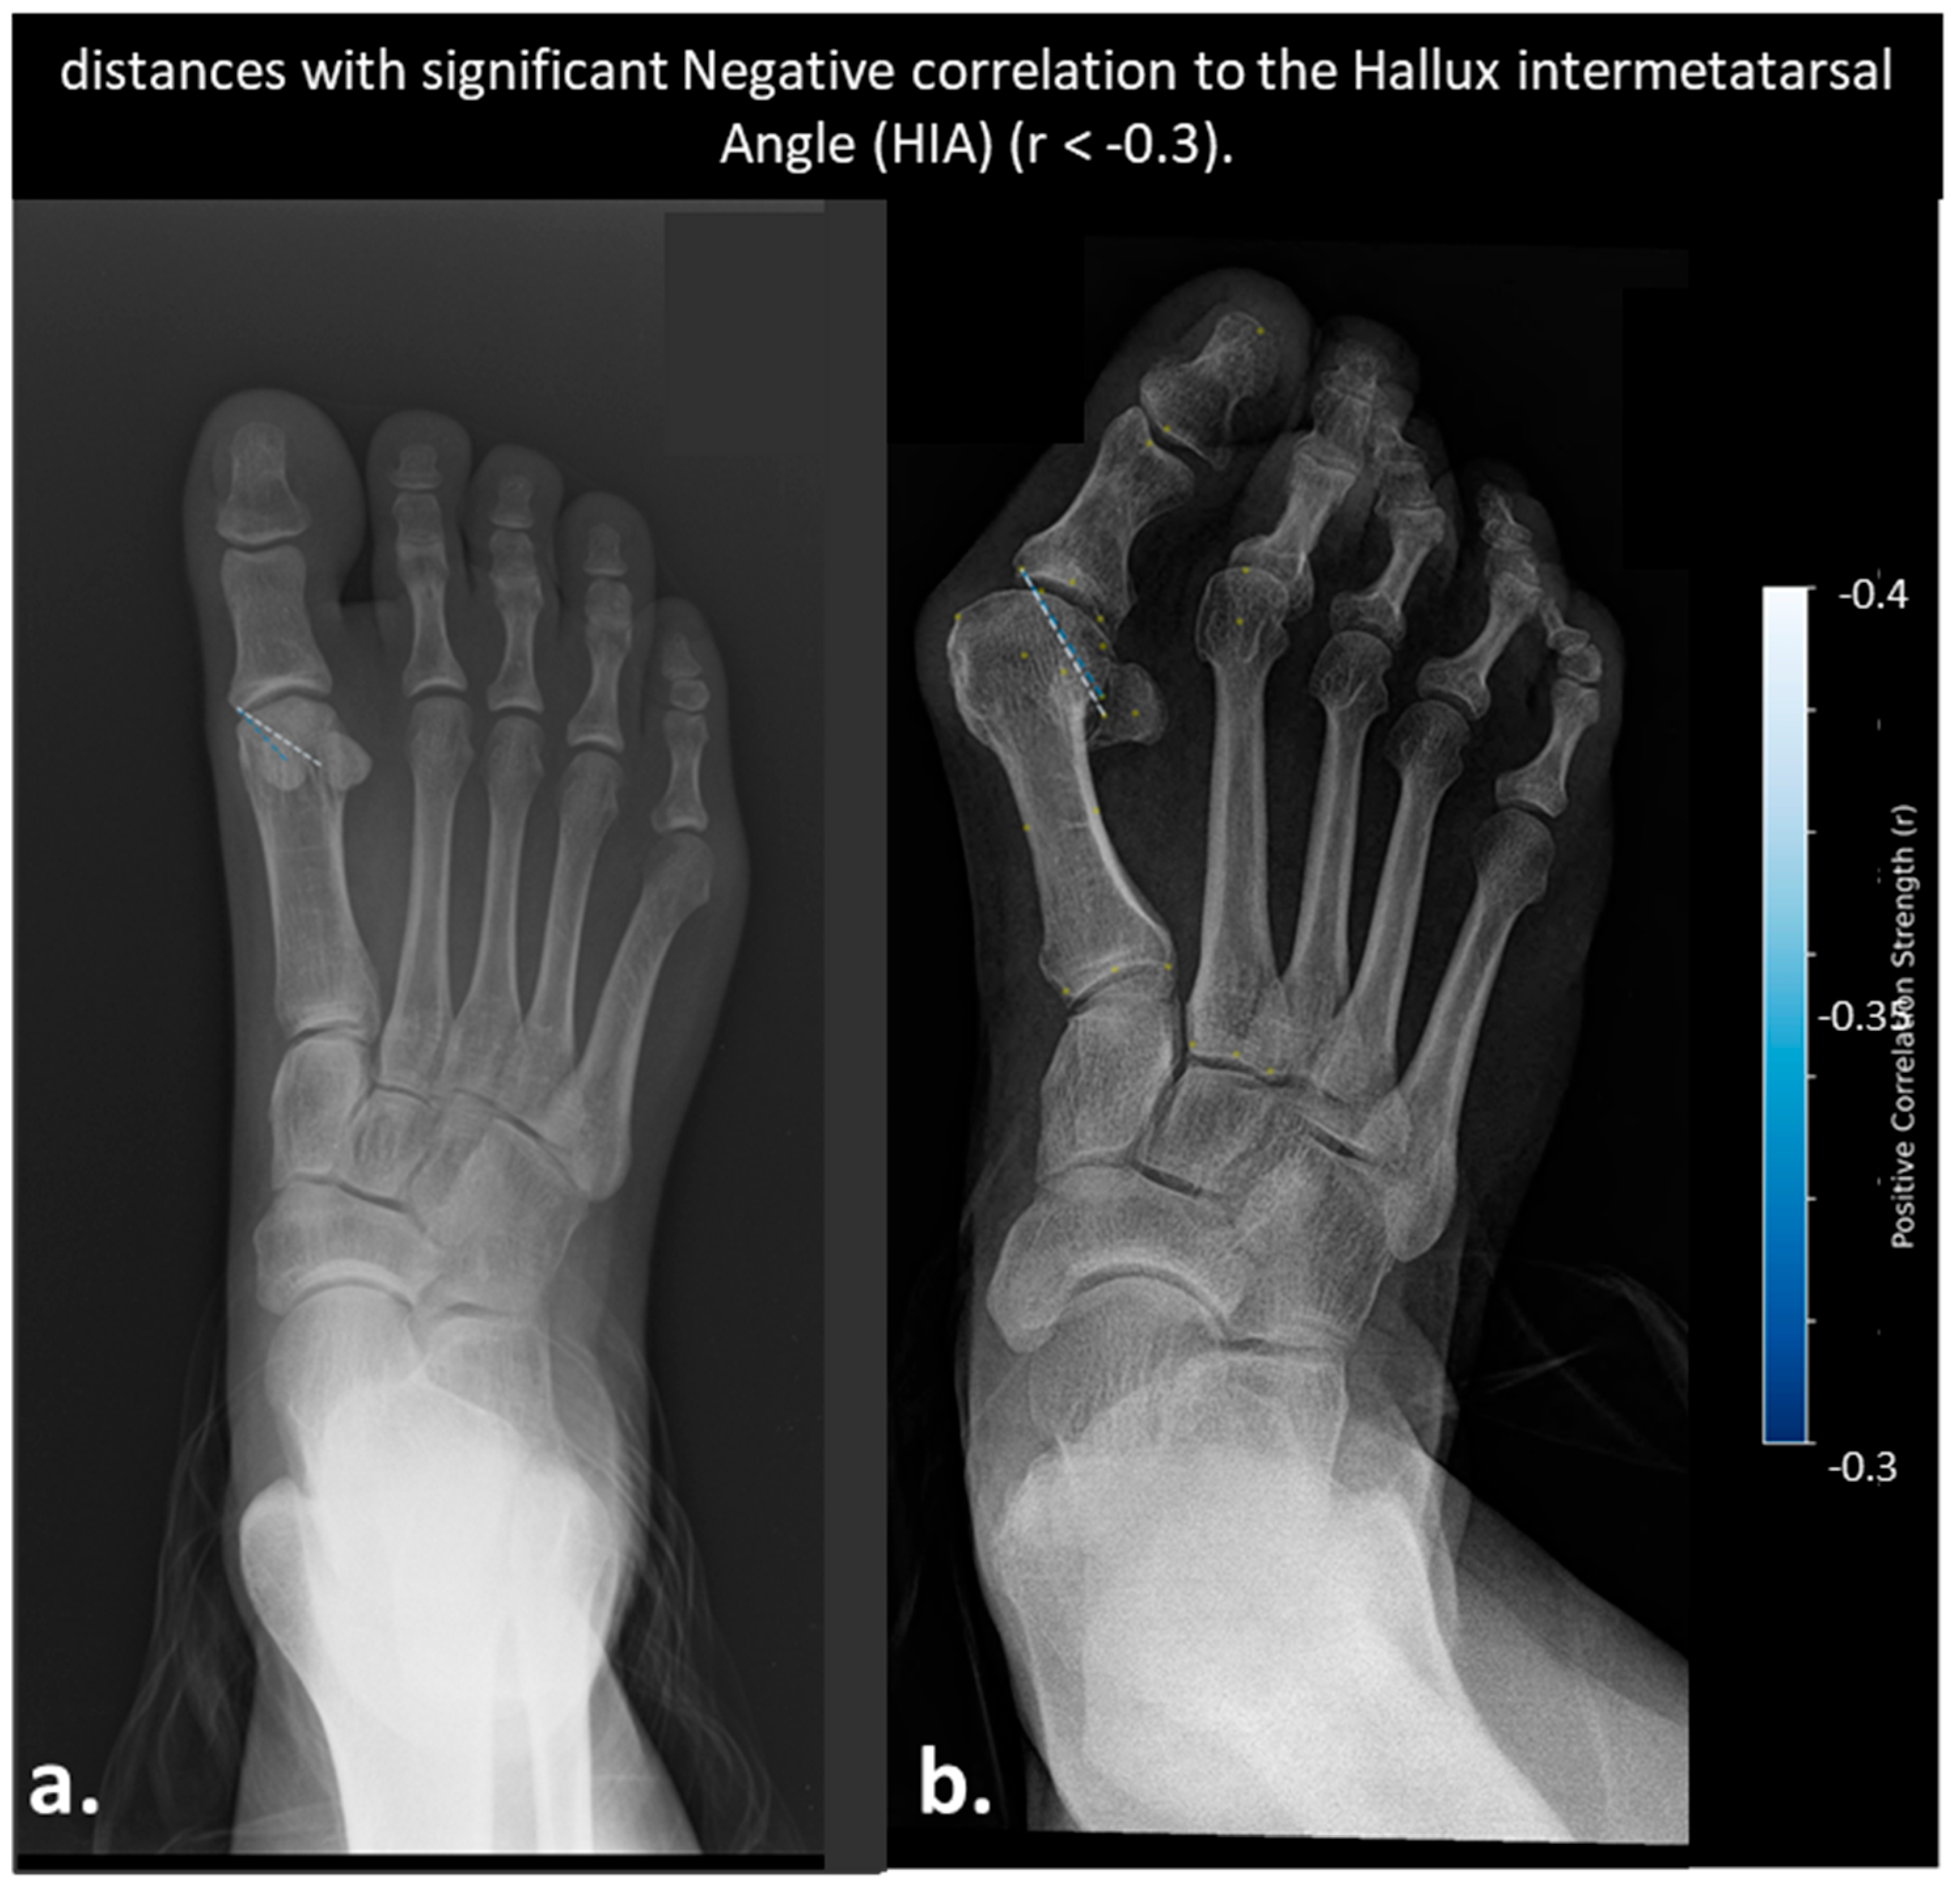

- Distances Correlated with Hallux Interphalangeal Angle (HIA)